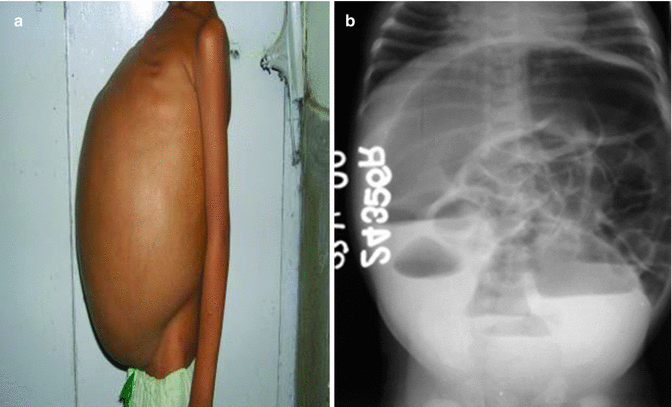

Hirschsprungs disease HD or HSCR is a birth defect in which nerves are missing from parts of the intestine. This may indicate a bowel blockage. Hirschsprung disease Abdominal x-ray.

The blockage is caused by a lack of nerves in the bottom segment of the colon. It occurs with an incidence of 14500 live births and demonstrates an overall 41 male-to-female ratio. Supine abdominal film demonstrates numerous dilated loops of bowel most likely down to the descending.

Radiography performed in children with Hirschsprungs disease yields findings similar to those in other forms of distal small intestine obstruction including variable gaseous distention of. Establishing the diagnosis also includes undergoing a number of diagnostic studies. The rectal biopsy is the best test to diagnose or rule out Hirschsprung disease.